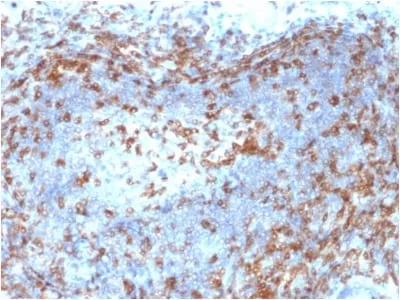

ZAP70 is a 70 kDa protein tyrosine kinase found in T-cells and natural killer cells. Control of this protein translation is via the IgVH gene.ZAP70 protein is expressed in leukemic cells of approximately 25% of chronic lymphocytic leukemia (CLL) cases as well. Anti-ZAP70 expression is an excellent surrogate marker for the distinction between the Ig-mutated (anti-ZAP70 negative) and Ig-unmutated (anti-ZAP70 positive) CLL subtypes and can identify patient groups with divergent clinical courses. The anti-ZAP70 positive Ig-unmutated CLL cases have been shown to have a poorer prognosis._x000D_ _x000D_ Primary antibodies are available purified, or with a selection of fluorescent CF® Dyes and other labels. CF® Dyes offer exceptional brightness and photostability. Note: Conjugates of blue fluorescent dyes like CF®405S and CF®405M are not recommended for detecting low abundance targets, because blue dyes have lower fluorescence and can give higher non-specific background than other dye colors._x000D_Synonyms:

IHC, FFPE (verified)Validated Applications:

IHC, FFPEField of Research:

ImmunologyPositive Control:

Jurkat cells. Tonsil or lymph node.Concentration: